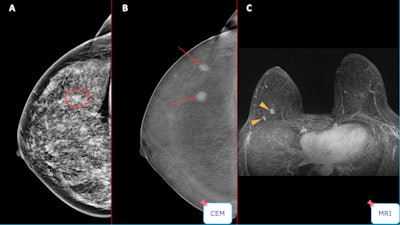

Case of a unifocal Luminal B invasive ductal carcinoma. Contrast-enhanced mammography shows better accuracy than conventional techniques in detecting these lesions, and this was confirmed by MRI study.